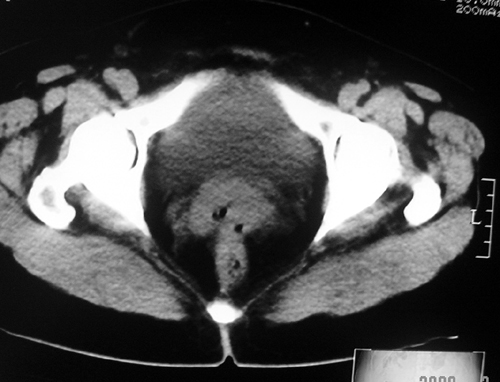

以下是引用余辉在2009-2-14 8:37:00的发言:[br]宫颈左后壁见较大低密度肿物影且向左后上方突出,宫腔内见大片状低密度区,考虑宫颈肿瘤,宫颈癌可能性大,伴宫腔积液或转移